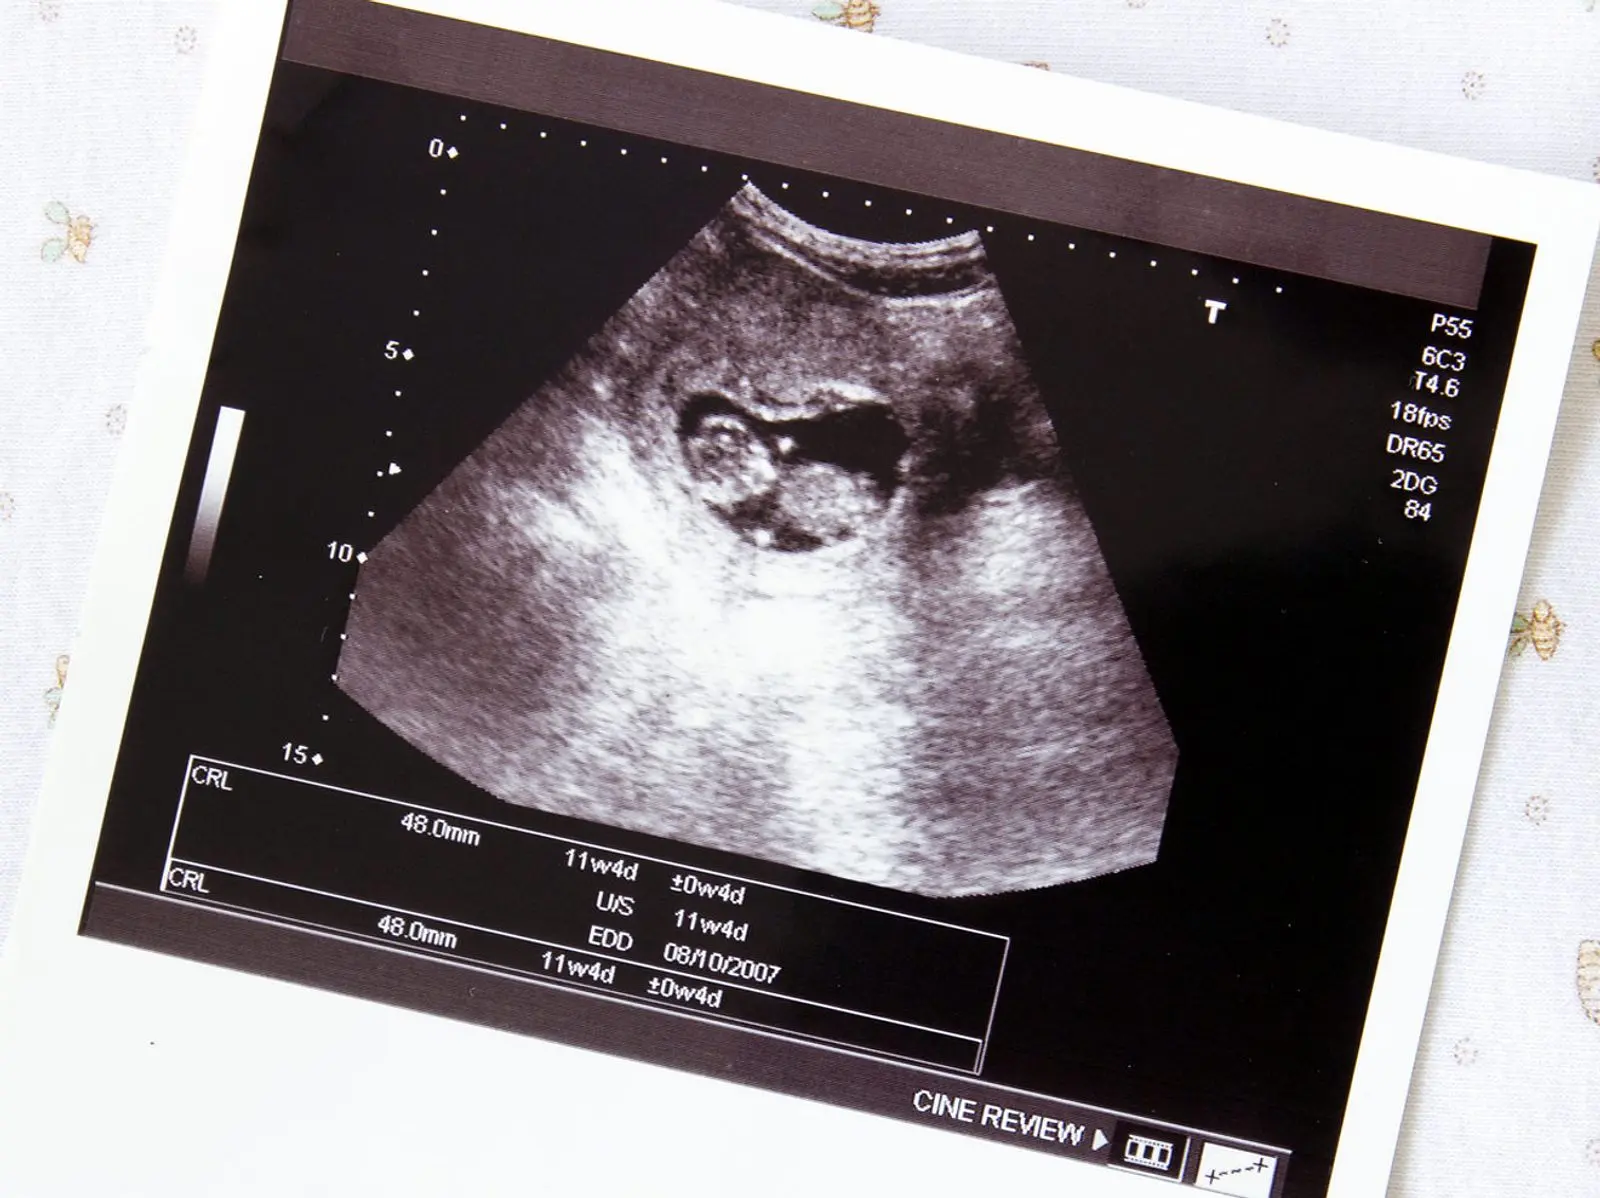

Beim Abortus imminens ist die Schwangerschaft noch intakt und kindliche Herztöne sind nachweisbar. Es kommt zu vaginalen Blutungen bei noch geschlossenem Muttermund. In diesem Fall muss es nicht zwangsläufig zu einer Fehlgeburt kommen. Eine frühzeitige medizinische Betreuung kann die Schwangerschaft in einigen Fällen retten.